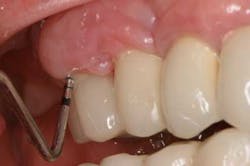

Fig. 4: Probing around implant-supported crown reveals depth and suppuration.